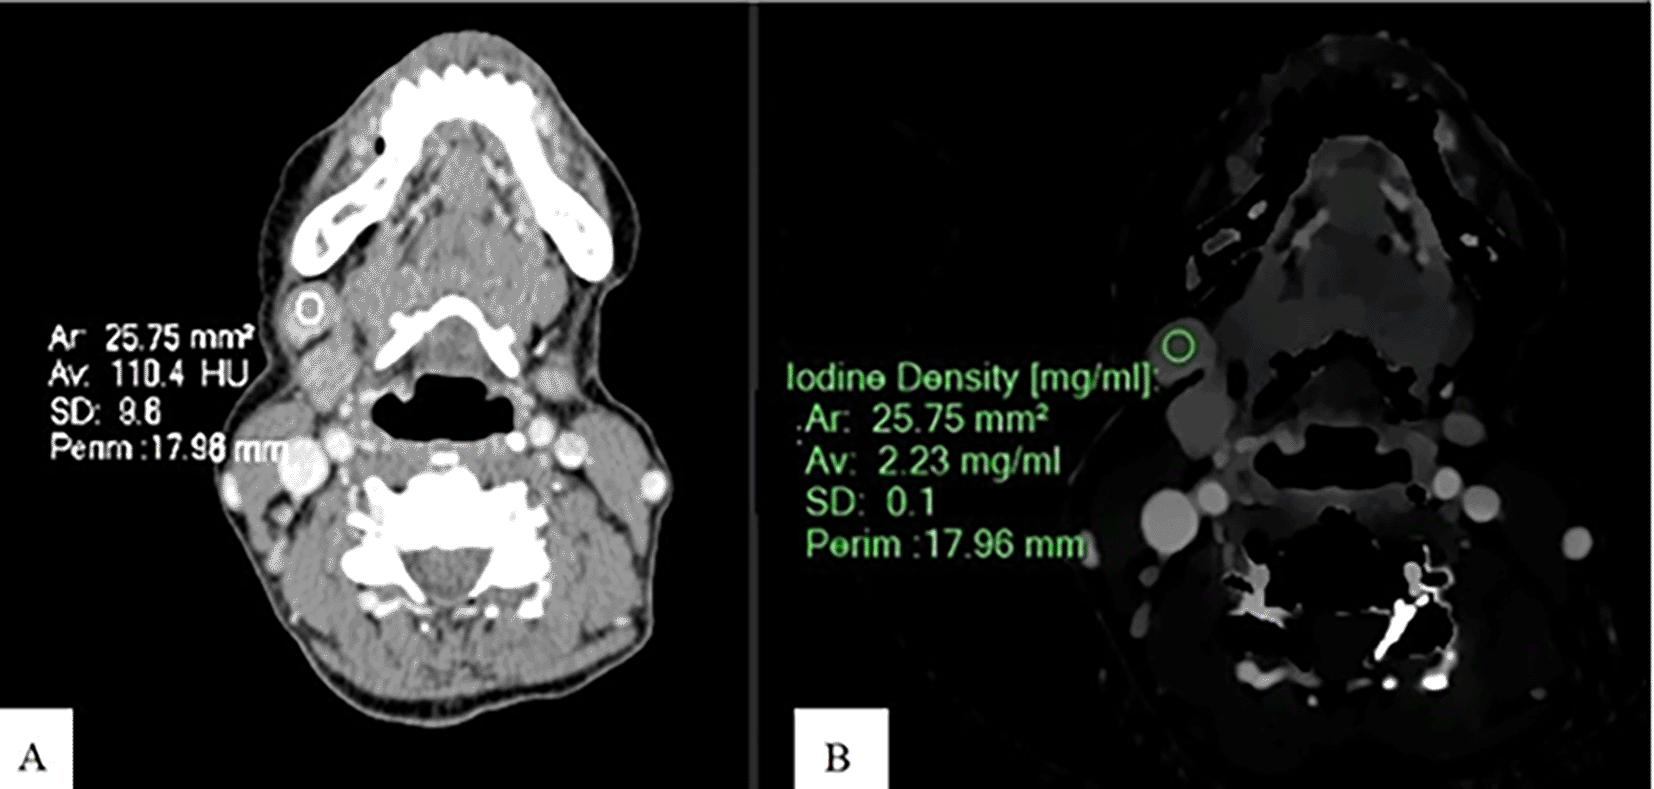

Spectral post-processing workstation (IntelliSpace Portal v11, Philips Healthcare, Netherlands) was used togenerateID and contrast-enhanced images (Figures 1, 2, and 3).

An Axial CT image of a patient with SCCA at gum shows CEAV measurement (110.4 HU) of the enlarged lymph node at left cervical level IB (A). An ID measurement (2.23 mg/ml) of this lymph node at the same CT level (B).